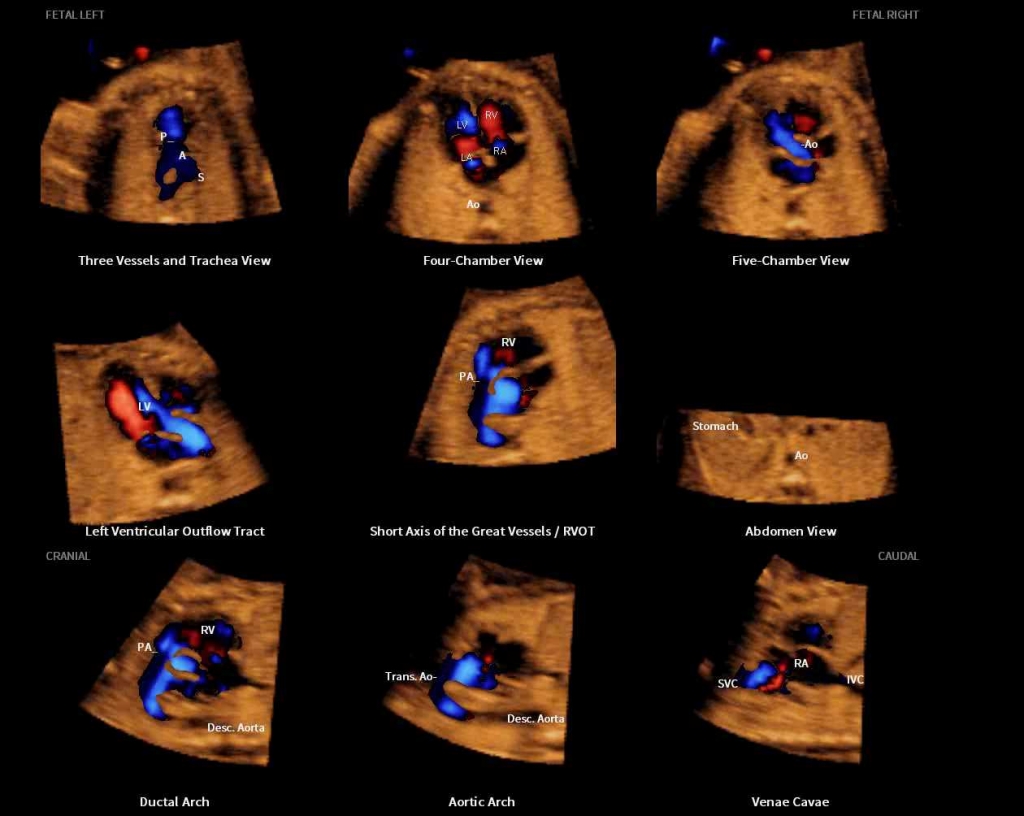

Samsung Presents Clinical Usability of its Ultrasound Imaging Technology at ISUOG 2017

Samsung Medison, a global medical equipment company and an affiliate of Samsung Electronics, is hosting a number of seminars at the 27th World Congress of the International Society of Ultrasound in Obstetrics & Gynecology (ISUOG) in Vienna. Through 13 sessions at Samsung’s Satellite Symposium, leading medical professionals are publicizing the clinical benefits of Samsung’s ultrasound imaging solutions for women’s health.